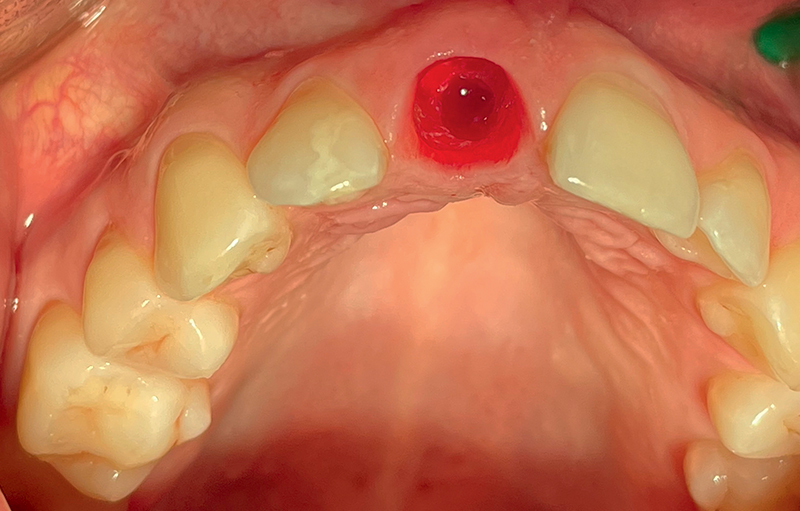

Fig. 2 (caso 1) - Vista clinica occlusale immediatamente dopo l'inserimento degli impianti in zirconia. Impianti SDS ovali nella regione anteriore, posizioni 11 e 21, fixtures classiche nelle posizioni 12 e 22, ed inserimento delle matrici PRF

Caso 1: Un paziente, maschio di 59 anni, si presentava con cisti apicali sugli incisivi centrali e laterali mascellari con trattamento canalare inadeguato. Seguiva posizionamento immediato di impianto in ceramica SDS con carico immediato per un periodo di 2 mesi. (Fig. 1,2).